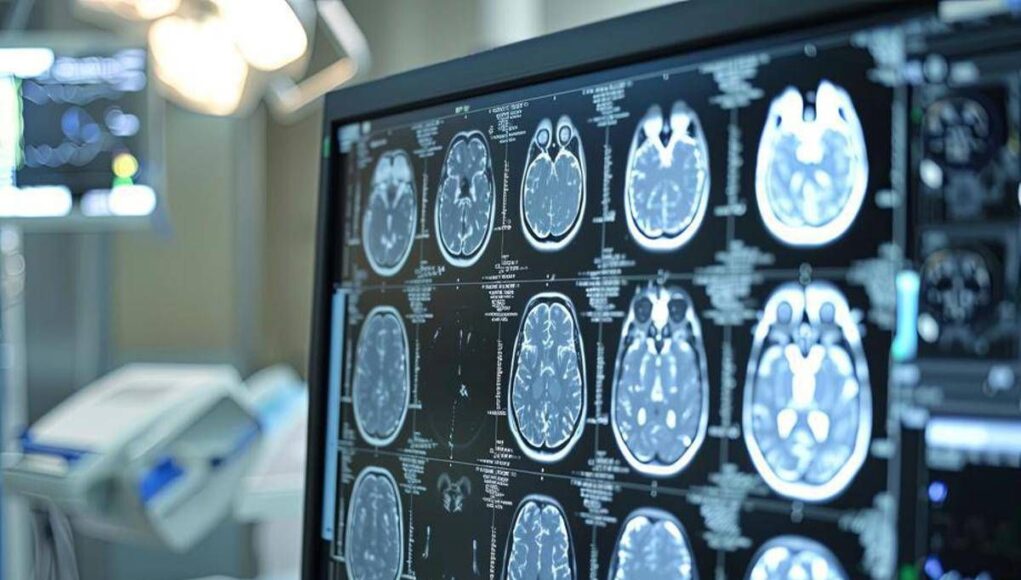

Lo Spoke viene così riconosciuto non come struttura “accessoria”, ma come elemento strategico del sistema, capace di trasformare la rete da concetto teorico a infrastruttura clinica funzionante. “Le malattie rare rappresentano una sfida clinica in continua evoluzione – ha sottolineato Maria Paola Campisi, dirigente medico Uoc Cardiologia P.O. Ingrassia Asp Palermo – Si tratta di un gruppo eterogeneo di patologie che, se non correttamente inquadrate e gestite, hanno un impatto significativo sulla morbilità e mortalità. Da qui l’importanza di creare una rete attraverso il ruolo dei centri Hub e Spoke sul territorio siciliano per garantire un accesso equo e tempestivo a tutti gli strumenti diagnostici avanzati (RMN, Medicina Nucleare, Genetica). Strategie concrete per la Sinergia tra Ospedale-territorio e la sostenibilità farmacologica per dare beneficio a tutti i nostri pazienti che convivono con queste patologie ancora oggi sotto diagnosticate”.